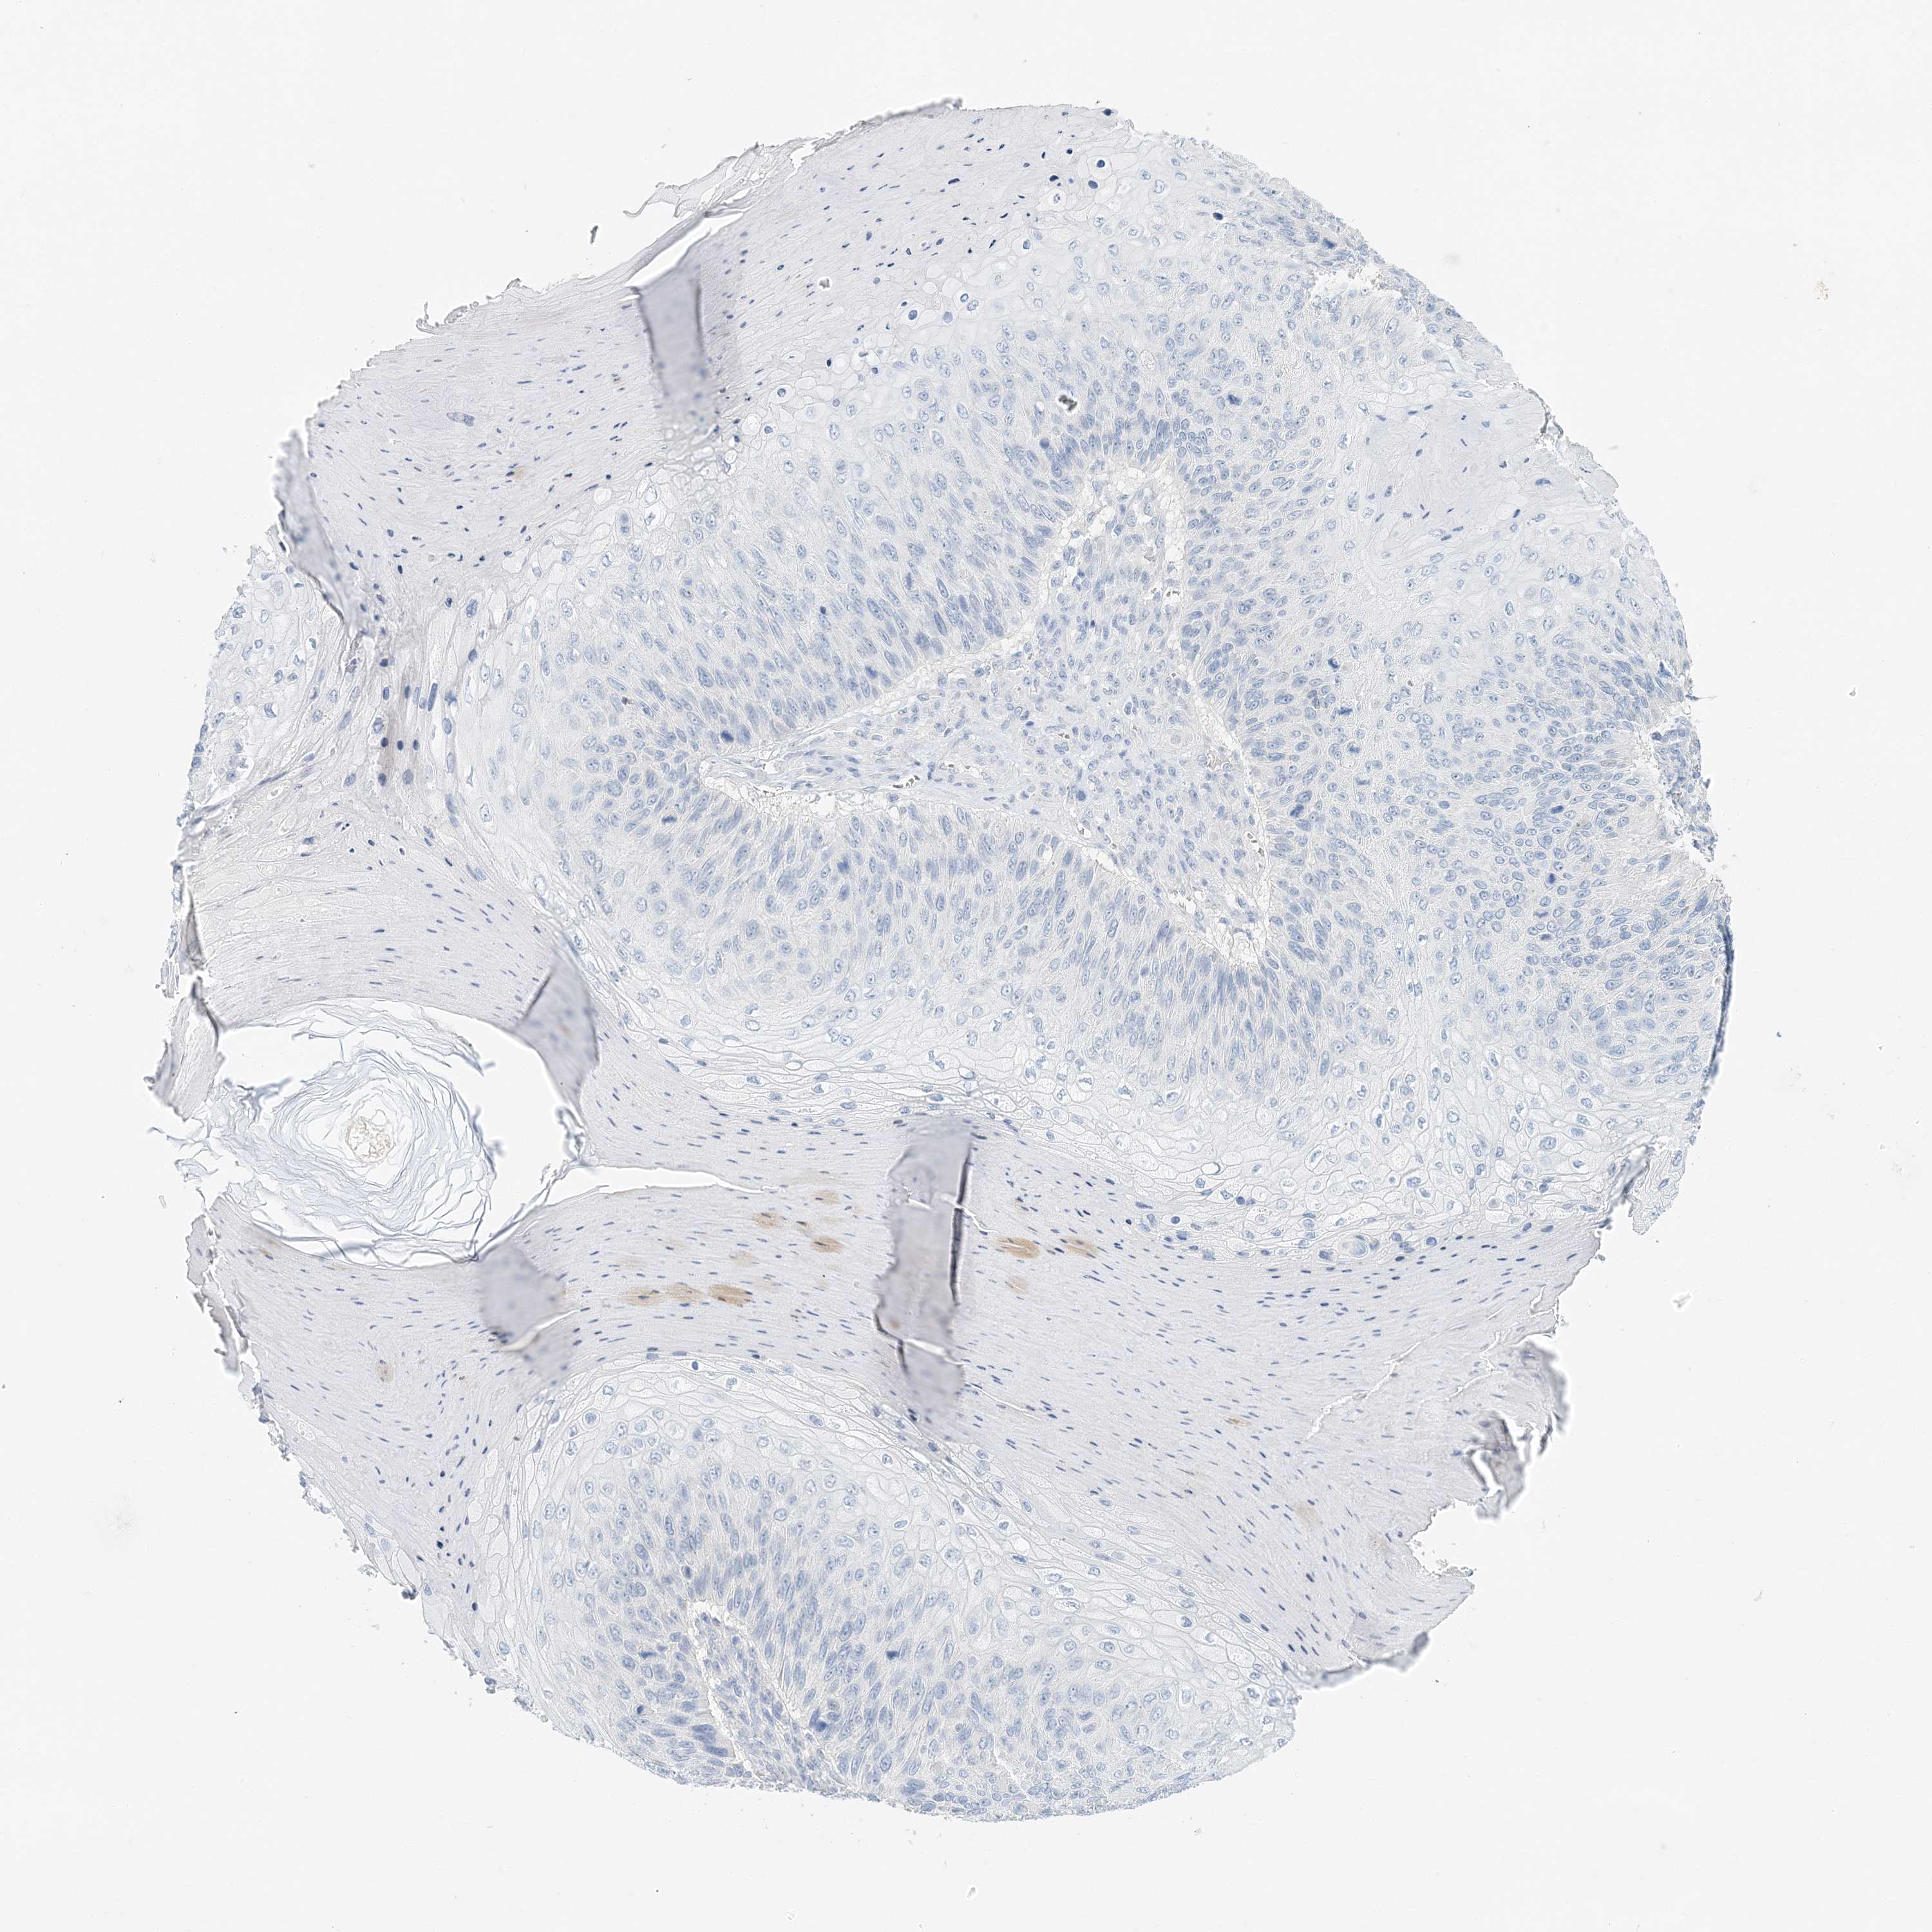

Basal cell and squamous cell cancer

SKIN CANCER - Protein expressioni

A mouse-over function shows sample information and annotation data. Click on an image to view it in a full screen mode. Samples can be filtered based on level of antibody staining by selecting one or several of the following categories: high, medium, low and not detected. The assay and annotation is described here.

Antibody stainingi

Antibody staining in the annotated cell types in the current human tissue is reported as not detected, low, medium, or high, based on conventional immunohistochemistry profiling in selected tissues. This score is based on the combination of the staining intensity and fraction of stained cells.

Each image is clickable and will lead to virtual microscopy that enables deeper exploration of all samples and also displays staining intensity scores, fraction scores and subcellular localization as well as patient and tissue information for each sample.

Antibody HPA035675

Squamous cell carcinoma, NOS